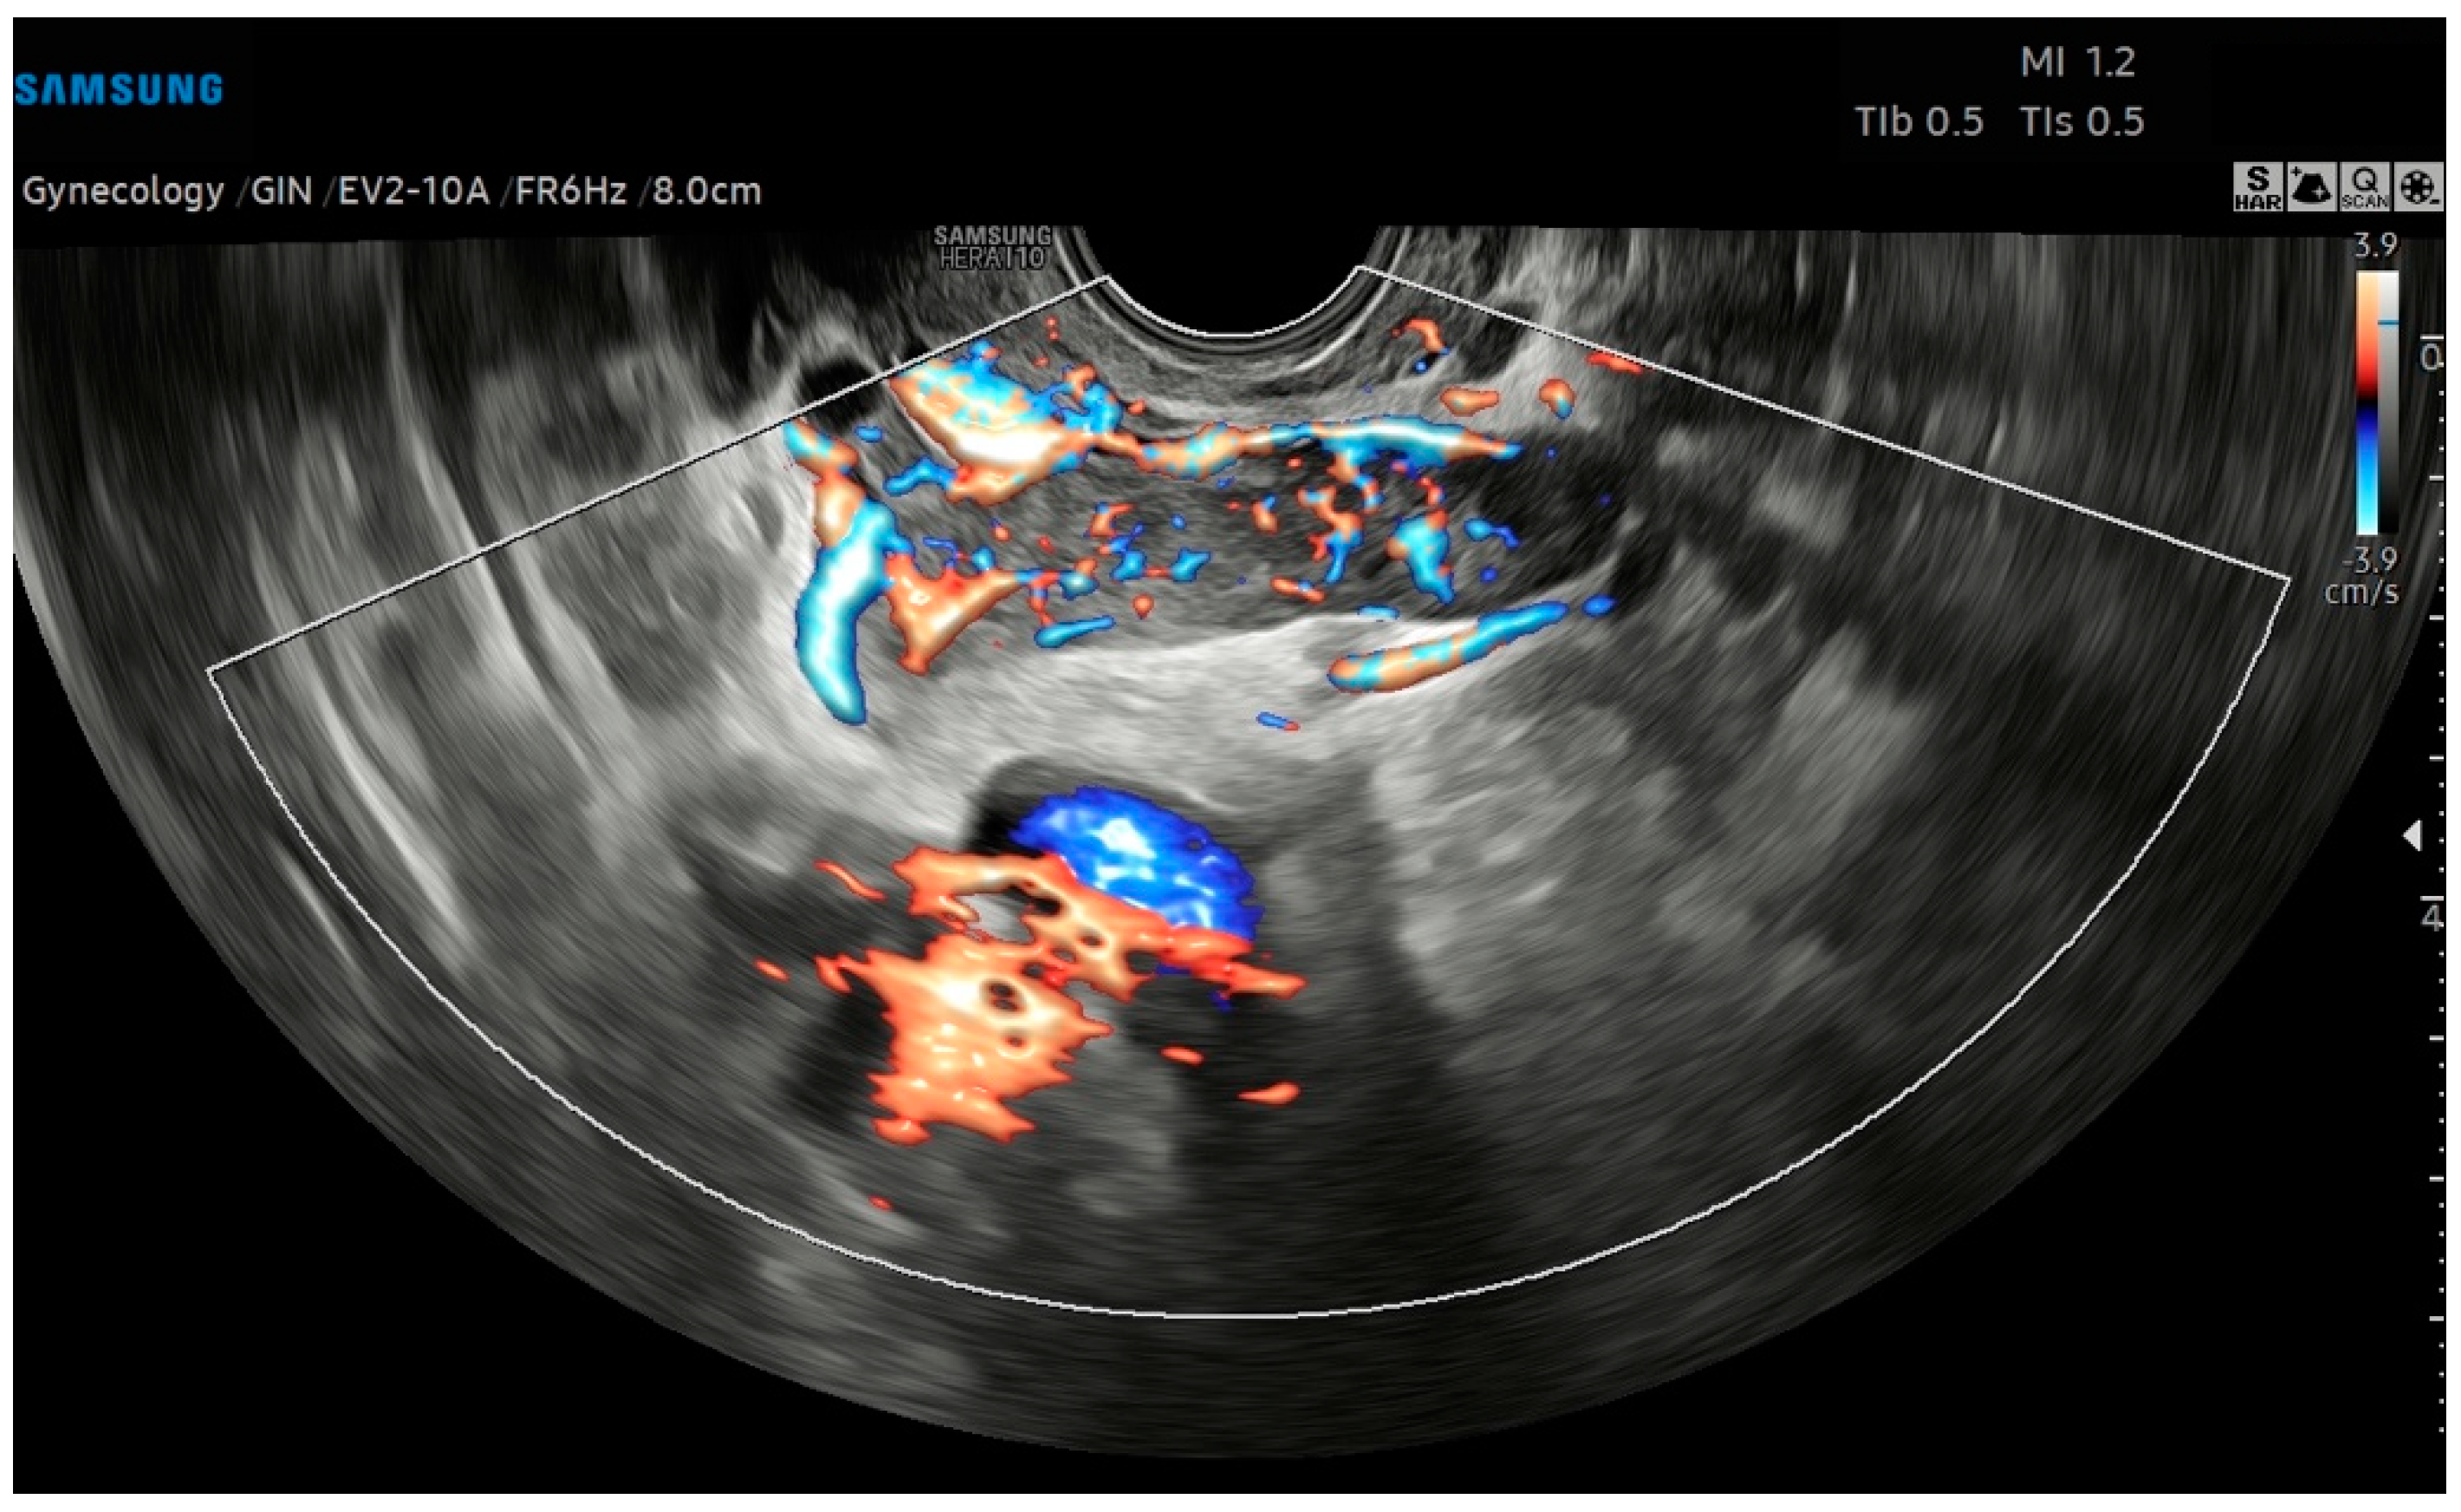

The preoperatory hypothesis was an atypical myoma or adenomyoma, in volumetric growth >50% compared to the previous control 3 months earlier. The adnexa, pouch of Douglas, pelvic peritoneum, and the pelvic tract of ureters were regular. On the left parauterine side, an elongated solid hypoechoic formation, with defined contours, abundant intralesional vascularization on the CD image (CS4), and extension toward the ovarian fossa, measuring 6.7 × 1.6 × 2.5 cm, was described (Figure 2). Pelvic Magnetic Resonance Imaging (RMI) confirmed the atypical myometrial lesion, without parauterine nor adnexal anomalies. Serum tumor markers (LDH, CEA, CA125, CA19.9, He4) were normal.

Figure 2. Transvaginal ultrasound with Color Doppler analysis; the longitudinal plane shows a solid elongated, hypoechoic, left parauterine mass. The Color Doppler analysis emphasizes the intense vascularization of the lesion.